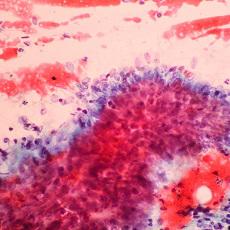

The cervix is the lower part of the uterus, the place where a baby grows during pregnancy. Cervical cancer is caused by a virus called HPV. The virus spreads through sexual contact. Most women's bodies are able to fight HPV infection. But sometimes the virus leads to cancer. You're at higher risk if you smoke, have had many children, use birth control pills for a long time, or have HIV infection.

Cervical cancer may not cause any symptoms at first. Later, you may have pelvic pain or bleeding from the vagina. It usually takes several years for normal cells in the cervix to turn into cancer cells. Your health care provider can find abnormal cells by doing a Pap test to examine cells from the cervix. You may also have an HPV test. If your results are abnormal, you may need a biopsy or other tests. By getting regular screenings, you can find and treat any problems before they turn into cancer.